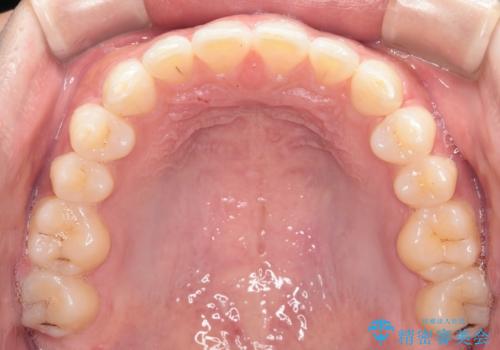

再矯正ということでがたつきはなくきれいに並んでいましたが、上下のアーチ(歯列弓)の大きさのバランスが悪く、結果的に後戻りの原因になってしまっていました。今回は下のアーチを小さくするためにIPRを行い、かみ合わせのバランスを治しながら前歯の隙間を閉じました。